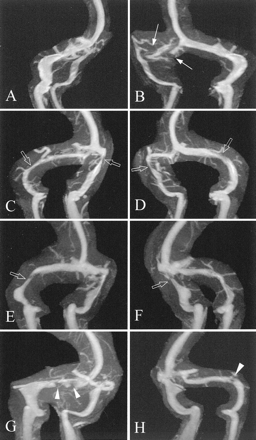

29例颅内高压症履行必要的标准也经历了ATECO造影术先生在我们的机构(表)。这些患者的平均年龄为37.2岁,男女比例1:2.6。图3说明了发现ATECO MRV的典型颅内高压症患者。

图3。Auto-triggered elliptic-centric-ordered三维gadolinium-enhanced先生造影术发现颅内高压症患者。老挝和饶分段最大强度投影(A和B)病人77;(C和D)病人36;和(E和F)病人8。(A)不连续(得分= 0)被认为在右侧横窦(箭头)(B)。extralumenal压狭窄的例子(打开箭头)在(B-F)。经管障碍物的例子被认为双边(箭头)病人69 (G和H)。